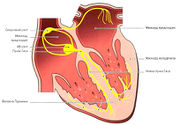

| 01:14, 20 июля 2016 | Mishci sport71.jpg (файл) |  |

46 КБ | Anes | Строение проводящей системы сердца | 1 |